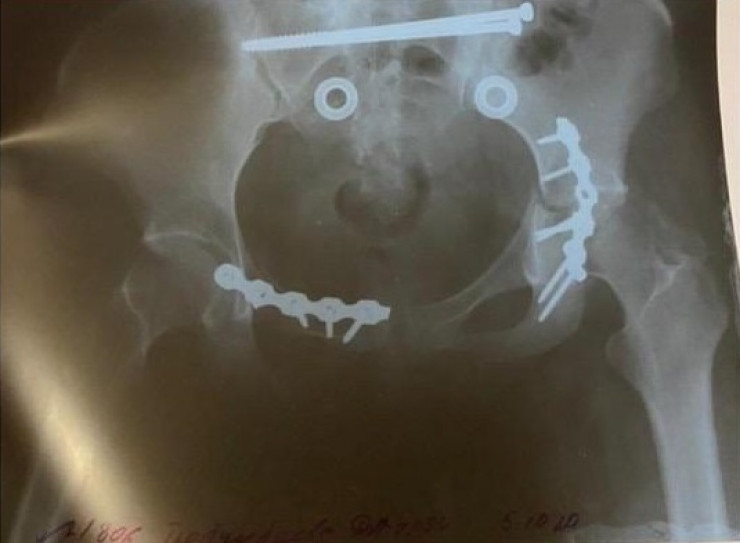

Врачи диагностировали у 25-летней Дарины множественный перелом таза. Два месяца она лежала, не вставая. Позже ей дали II группу инвалидности. Дети на момент ДТП были в возрасте трех и одного года.